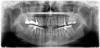

Bier Опубликовано 19 ноября, 2012 Поделиться Опубликовано 19 ноября, 2012 Мало что понятно, все пятерки и четверки у вас на месте. Справа нужен с. лифтинг, слева не нужен. Ссылка на комментарий

Acubed Опубликовано 25 ноября, 2012 Автор Поделиться Опубликовано 25 ноября, 2012 Мало что понятно, все пятерки и четверки у вас на месте. Справа нужен с. лифтинг, слева не нужен.На самом деле пятерка справа сверху - это лишь корешок, который был с трещенкой и который мне спасали именно для возможности установки моста (иначе пришлось бы зацепить здоровую нетронутую четверку) Ссылка на комментарий

Bier Опубликовано 25 ноября, 2012 Поделиться Опубликовано 25 ноября, 2012 Слева у вас зубы сдвинулись и места для имплантата нет. Тут комплексный план лечения нужен. А не наездами в Россию. Нижние 6ки - удалять нужно. Ссылка на комментарий